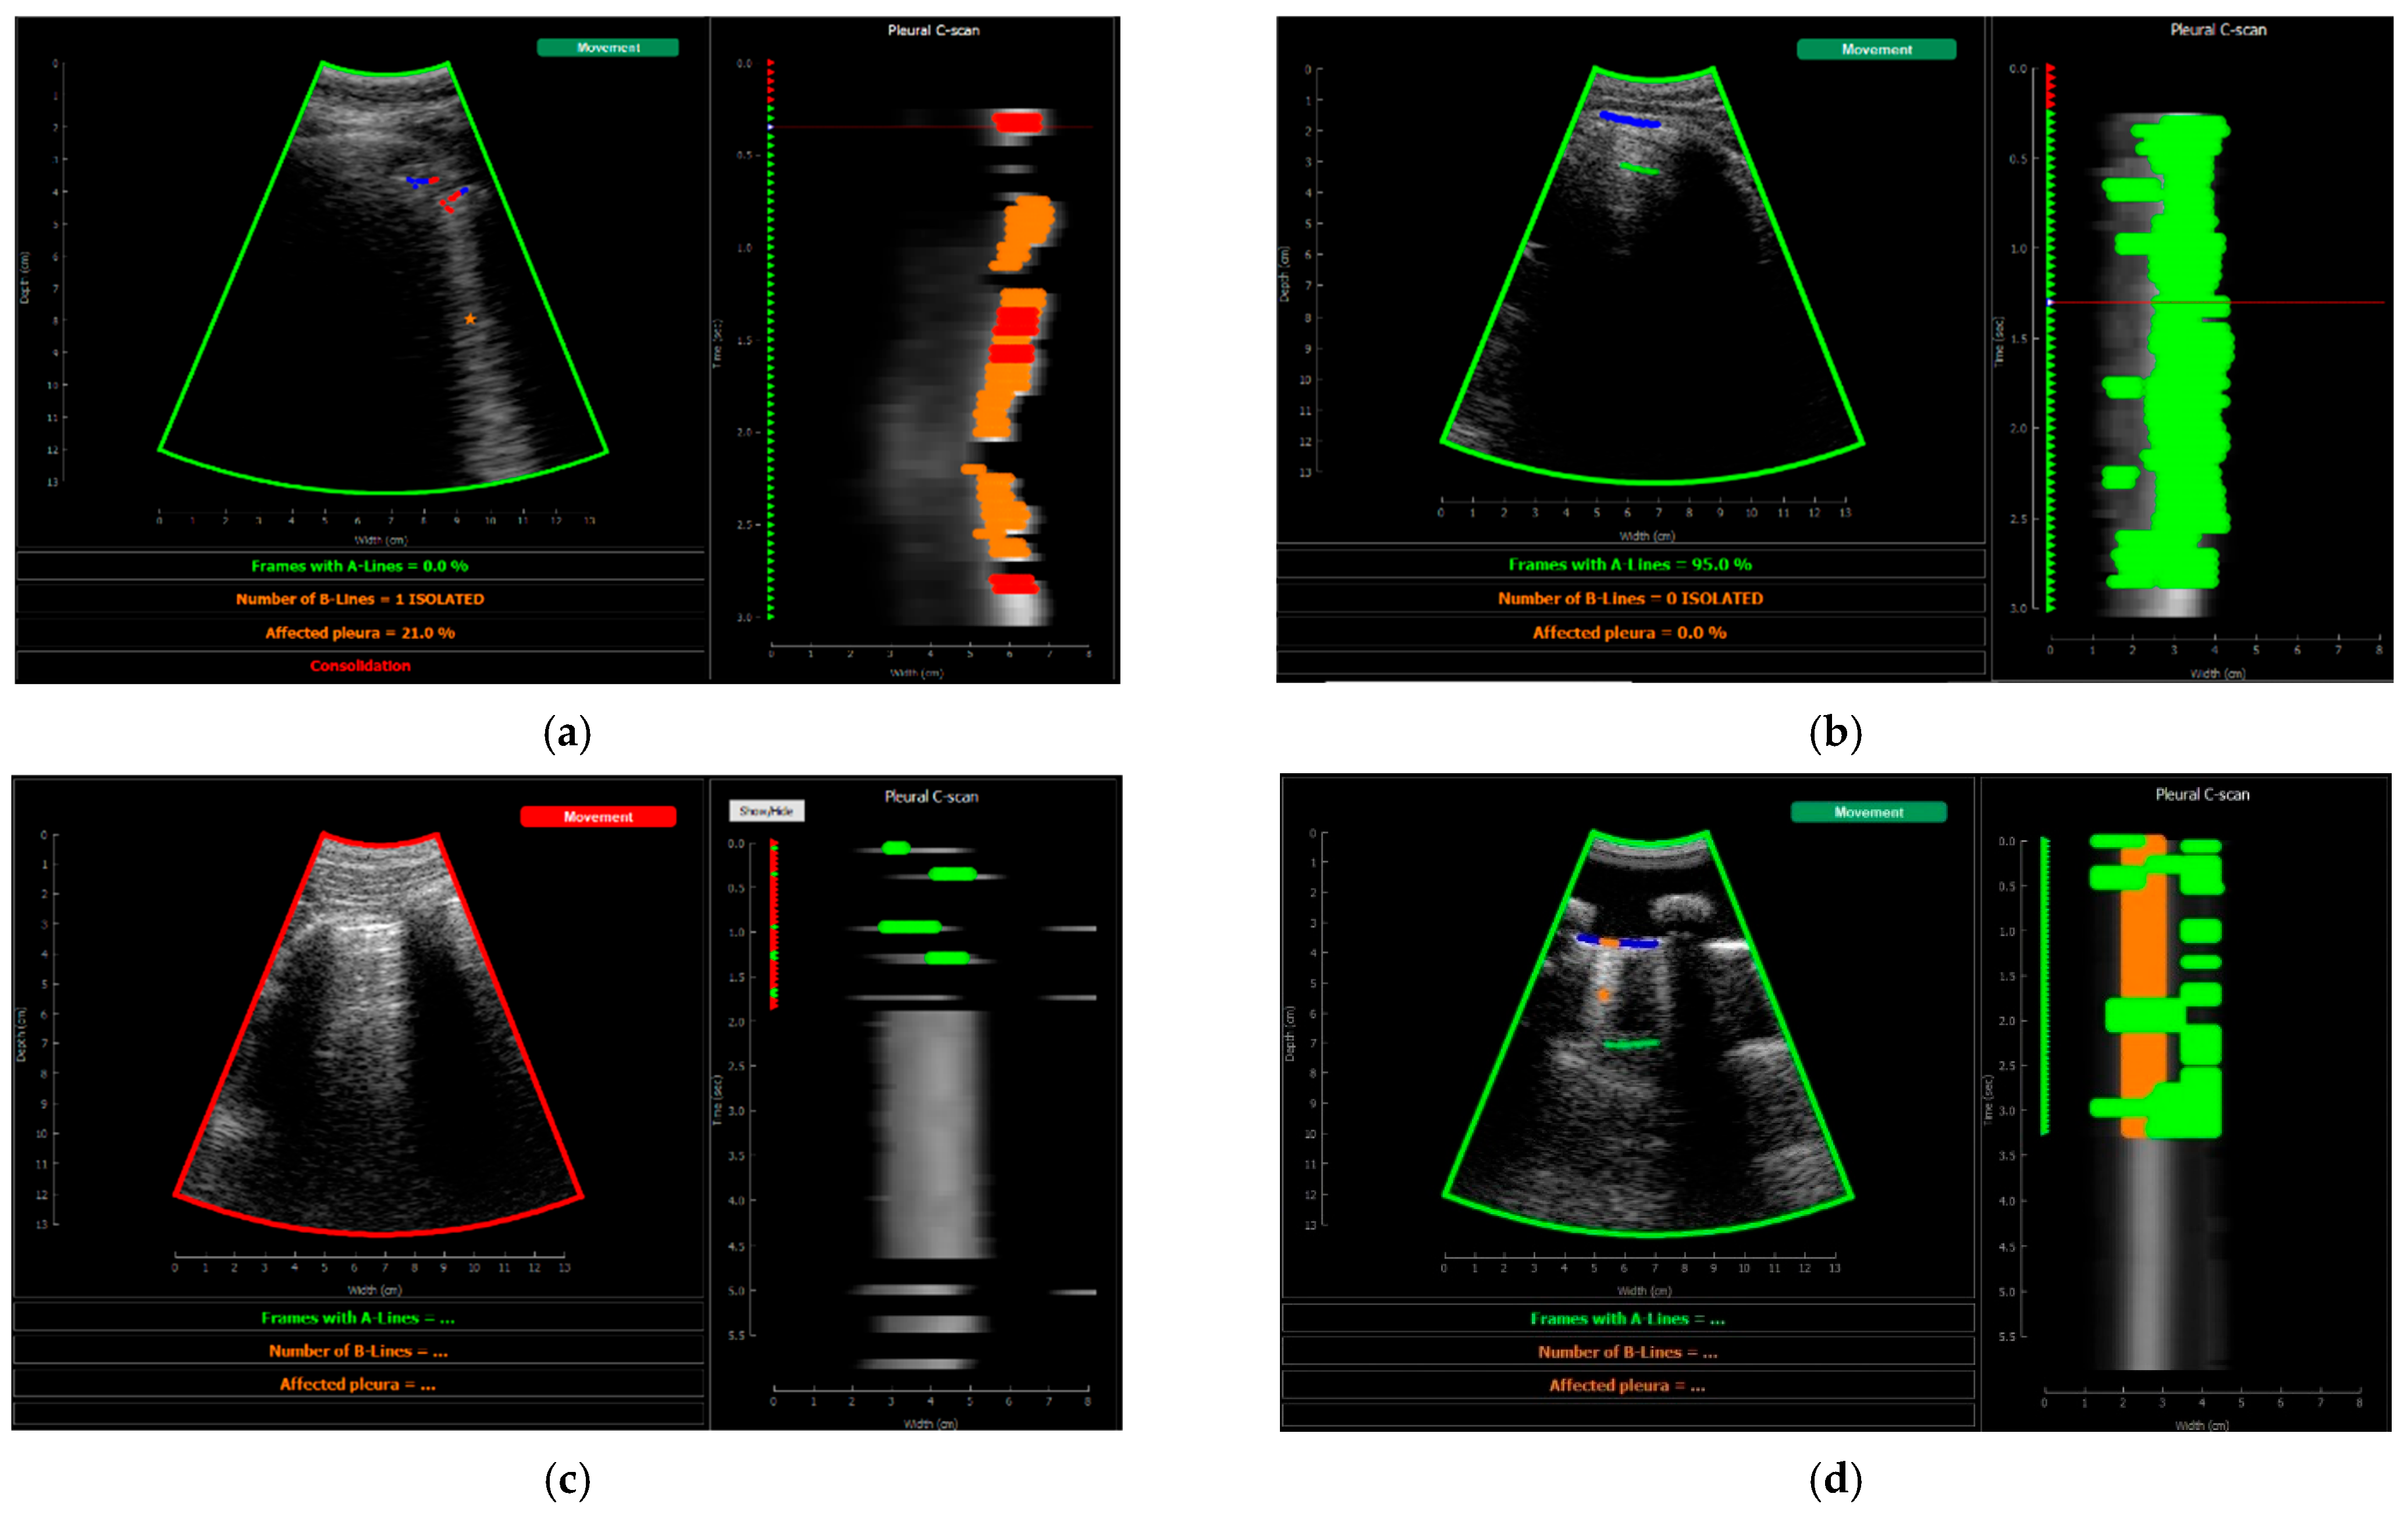

2.2.2. Neural Network Output Data

Labelling Tools

CNN Output

3.1. Model Results